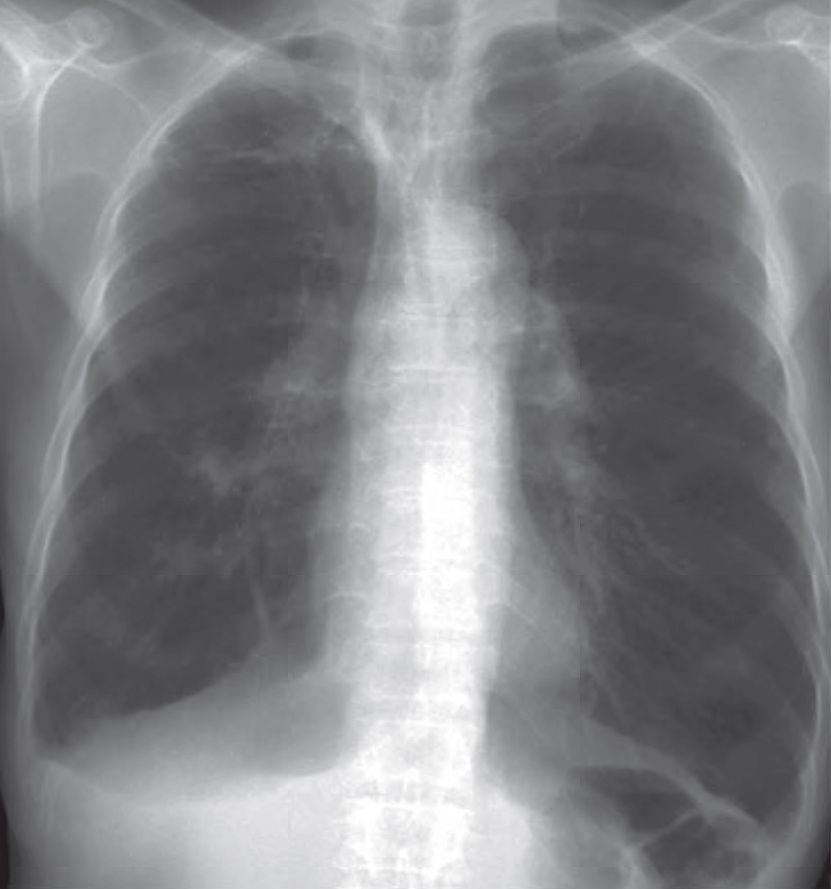

Chest X-Ray Interpretation

- Hyperinflated, hyperlucent lungs

- Flat diaphragm

Diagnosis: COPD (Emphysema)